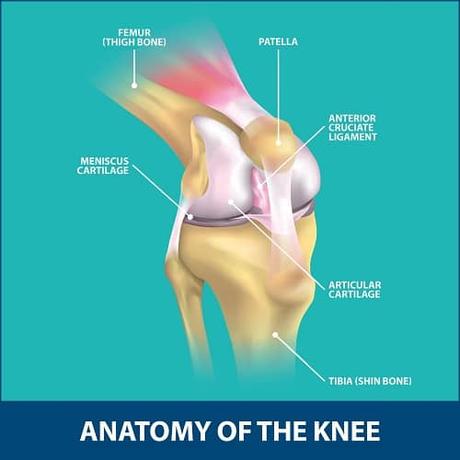

The knee is one of the most important and complex joints in the human body.

It allows us to walk, run, jump, and bend our legs.

The knee is made up of four bones:

the femur (thigh bone), the tibia (shin bone), the fibula (smaller bone next to the tibia), and the patella (kneecap).

The patella is a small, flat bone that covers and protects the front of the knee joint.

It also helps to increase the leverage and efficiency of the muscles that extend the knee.